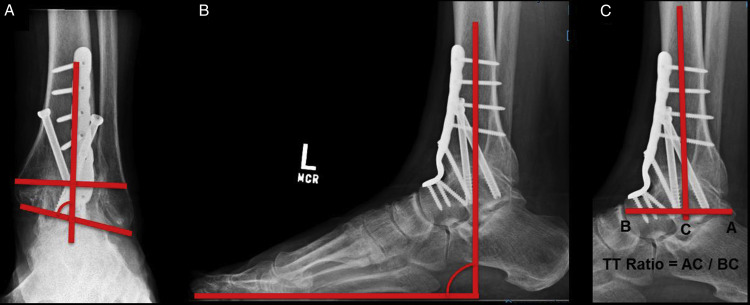

Total ankle implants are now more anatomical than they were in the past. This implies that they recreate the natural architecture of the ankle while only removing a little amount of bone tissue. Instruments for performing the procedure have also advanced dramatically, allowing orthopedic surgeons to be more precise and reliable in their work.

The medical community’s grasp of how to align the ligaments of the ankle and position the foot below the ankle after ankle replacement has also advanced significantly. Patients who get an ankle replacement have had improved results as a result of all of these considerations.